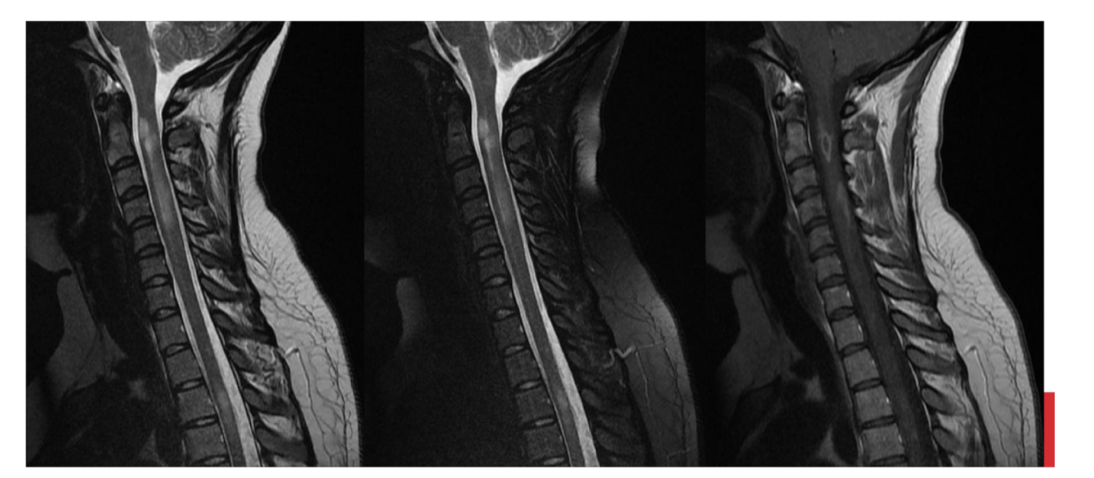

Sequences + Pathology

• T2, T2FS, T1C+

• Path = multiple sclerosis

• Increased signal within the spinal cord confirming the presence of lesions

79